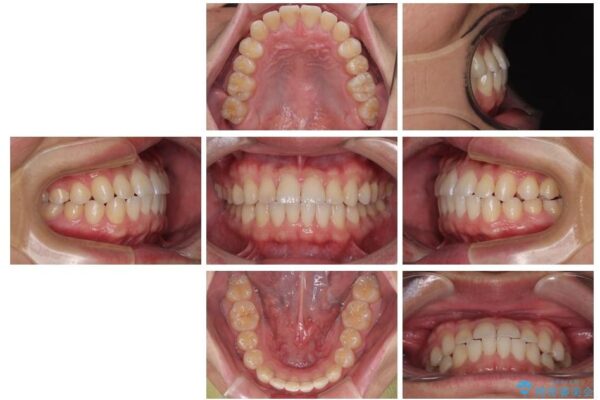

**前歯のデコボコ(叢生)**が整い、歯列全体が美しく改善

シザーズバイトの奥歯も正常なかみ合わせに改善

捻転歯も回転が修正され、全体的に清掃性・咀嚼効率が向上

治療後

• 前歯のガタガタ・奥歯のかみ合わせ(シザーズバイト)を改善|1年半で完了したメタルブラケット矯正 治療後画像